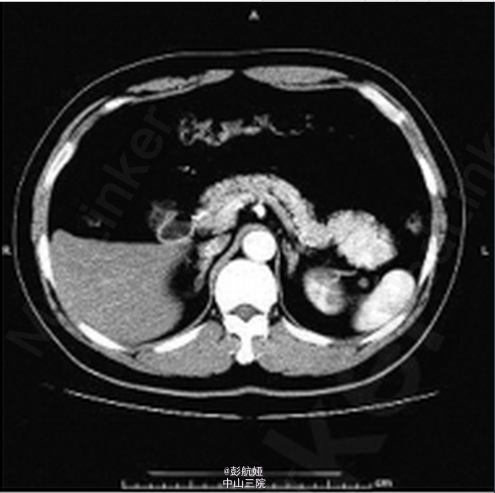

患者 ,男 ,56岁 ,因“体检发现胰尾部占位 2周”入院 ,入院后无明显阳性体征 。 实验室检查 :肿瘤标志物甲胎蛋白6.57ng/mL ,癌胚抗原 3.64ng/mL ,糖类抗原1259.90U/mL ,糖 链抗原 19-912.30 U/mL ,鳞状细胞癌相关抗原0.8ng/mL 。B超检查 :胰腺切面形态失常 ,胰尾部可见一大小3.5 cm × 2.8cm 低回声区 ,边界尚清 ,内部回声不均。胰管不扩张。 彩色多 普勒(CDFI) :门静脉血流充盈 ,上述胰尾部低回声区内未见明显血流信号 ,余部位未见异常血流信号 。 B 超诊断 :胰尾部实质性病灶 。 CT 增强检查 :胰腺尾部可见一肿块影 ,大小约 4.4cm × 3.4 cm × 2.4 cm ,动脉期 、静脉期明显强化(图1、2) ,延迟期强化程度减低 ,且均匀强化(图 3) ,胰尾向前推移 ,肿块位于脾动静脉前下方 ,胰管未见扩张 。脾脏不大 ,密度均匀。 CT 诊断 :胰尾后方肿块、强化 ,多考虑肿瘤性病变 。手术及病理 :行全腹腔镜下胰体尾切除术 。切开胃结肠韧带 ,显露胰腺 ,可见胰腺体尾部约 5 cm × 3 cm 肿块 ,凸向胰体尾背侧生长 ,脾血管未受侵犯。 行胰体尾切除。病理 :送检组织镜下见为基本正常的胰腺组织 ,部分包裹脾脏组织 ,脾小体结构清楚 。符合(胰体尾)副脾 。